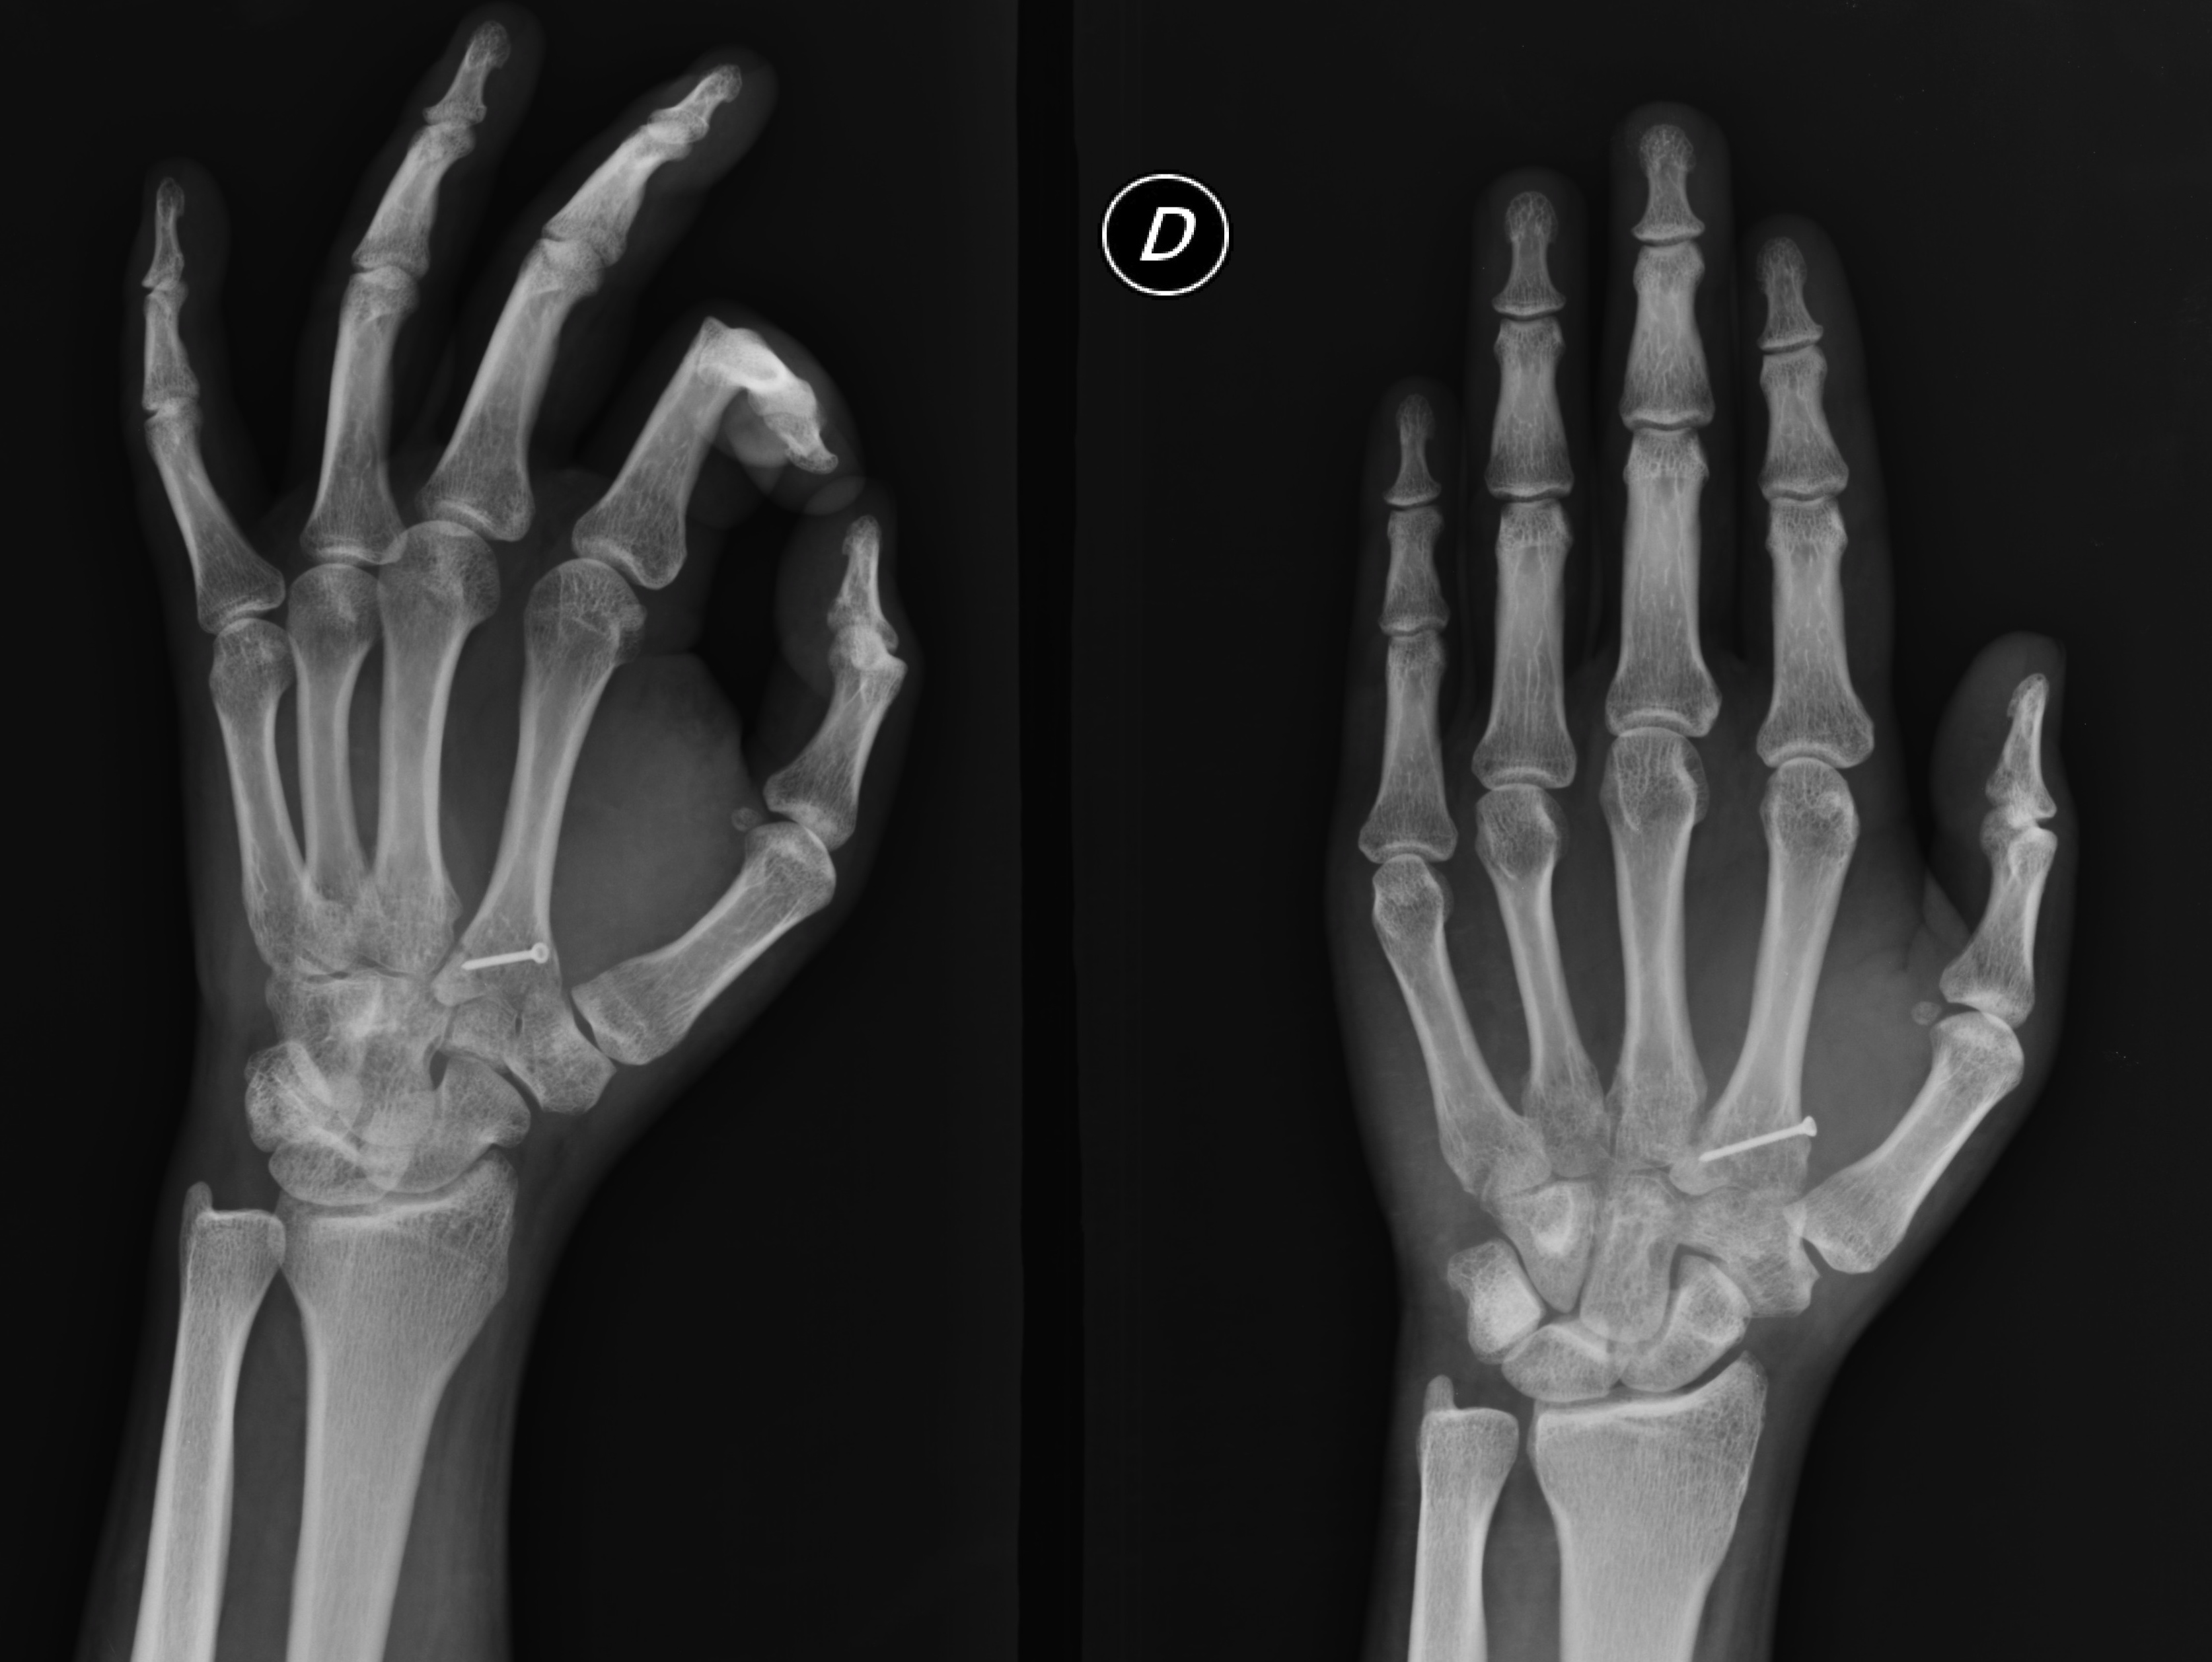

Fractura del cóndilo cubital de la base del 2do metacarpiano con desplazamiento a palmar. Presentación de un caso